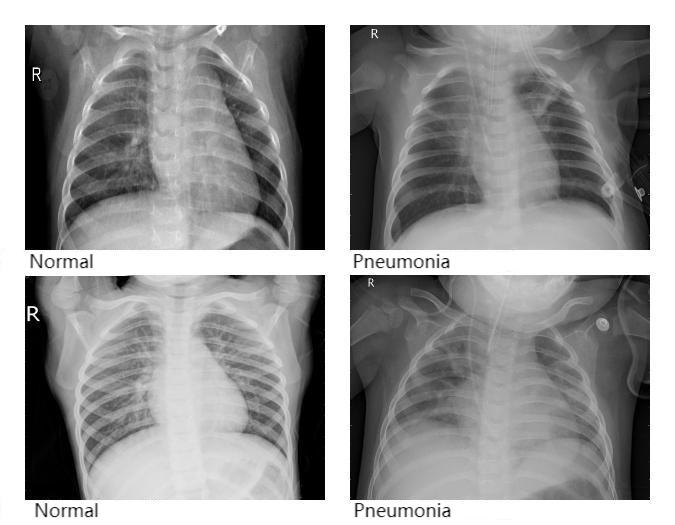

Because pneumonia incidence remains high and traditional diagnostic methods face efficiency bottlenecks, and since convolutional neural networks are increasingly applied in medical image analysis, this paper employs the AlexNet model to analyze chest X-ray images for pneumonia detection. The study optimizes the training process by tuning the number of epochs to identify the model with the best accuracy. Experimental results show that the model achieved an accuracy of 0.8108 (81.08%), demonstrating good capability for recognizing pneumonia in X-ray images. This method can help reduce the bias and time required by manual interpretation, effectively improve the efficiency of pneumonia screening, and gain valuable time for timely diagnosis and treatment.